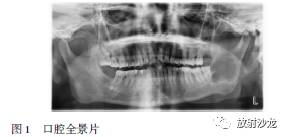

X线曲面断层片(见图1)示:左下颌骨体部至下颌升支乙状切迹可见多房透光影,边缘不规则,38远中根有吸收现象。低密度透光影上界至下颌骨乙状切迹,下界至下颌骨下缘,前界至38远中,后界至下颌升支后缘。